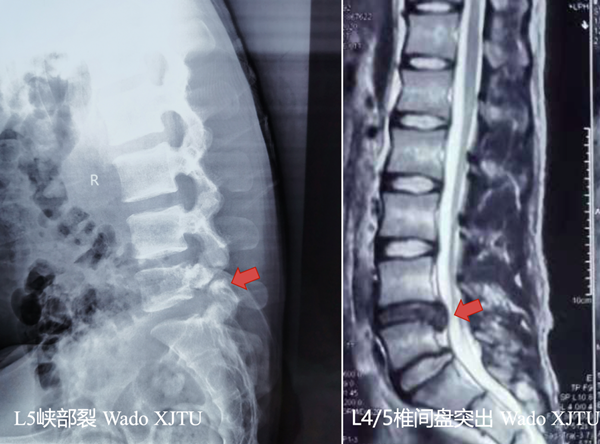

20岁男性患者,腰痛不适伴右下肢抽痛2月余,保守治疗效果不佳,慕名来到我院。骨二科王栋教授接诊了该患者,经过仔细询问病史及体格检查,完善相关影像学检查后,患者确诊为:腰椎间盘突出症(L4/5);腰5椎弓根峡部裂。

术前患者病变影像

目前临床上针对此型病例,多采用传统的开放手术,即后方入路或椎间孔入路切开减压植骨融合内固定术(PLIF ,TLIF手术)。经治疗组认真讨论,考虑该患者较年轻,治疗组为该患者选择了脊柱内镜下的ENDO-TLIF/PLIF手术。应用脊椎内镜PLUS系统下的腰4/5,腰5/骶1椎间盘切除,椎管减压,植骨融合,经皮后路椎弓根螺钉内固定术,该术式属于内镜下微创手术,通过关节突及椎板的有限磨除,即可达到椎间盘切除及融合固定的手术目的,具有创伤小,早期恢复正常生活。此种术式难度较大,需要一定的脊柱内镜手术经验积累,目前国内仅有少数医院开展。